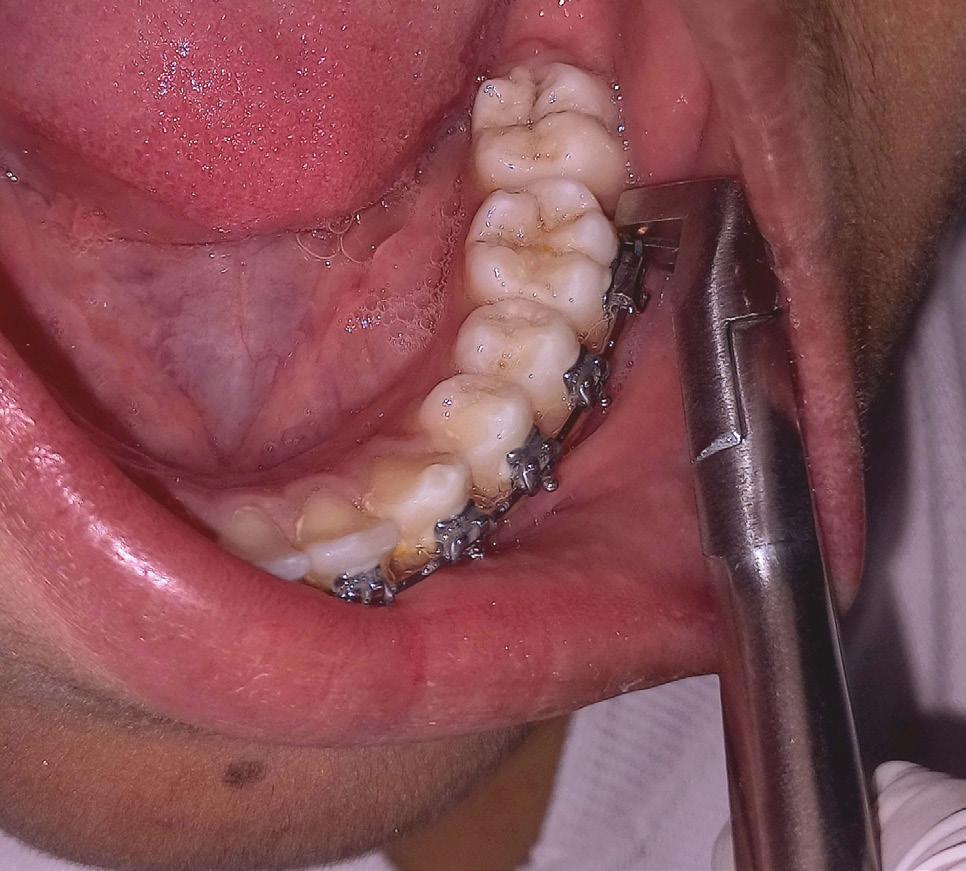

Given the clinical and radiographic presentations, the treatment plan to surgically extract the developing third molars prior to orthodontic treatment was presented to the patient and parents for their consent. The mandibular third molars were surgically removed by an oral surgeon under deep sedation. A follow-up panoramic radiograph obtained approximately 7 months following the surgery, at 12 years and 7 months of age, revealed completely healed third molar extraction sites, spontaneous improvement in the angulation of the left mandibular second molar but little change in the angulation of the right second molar. Orthodontic records were obtained at this stage and treatment was initiated with complete maxillary and mandibular orthodontic MBT, 0.022’’ slot size brackets. Orthodontic bands were placed on the mandibular first permanent molars that were modified with laboratory soldered Halterman appliances from the lingual surfaces of the bands. Orthodontic buttons were bonded on the occlusal surfaces of the impacted molars. Initial disimpaction of the second molars was achieved by sequential distal traction with the use of chain elastics. When the molars were sufficiently uprighted and the buccal surfaces were visible, orthodontic direct-bond brackets were placed and the Halterman arm and occlusal buttons were removed. All further orthodontic tooth movements including uprighting of the second molars were achieved through 4-6-weekly sequential changes of Nickel-Titanium followed by stainless steel archwires. The sequence of archwires were as follows: Ni-Ti0.012”, 0.014”, 0.016”, 0.018” 0.016x0.022”, 0.017x0.025 and SS- 0.016x0.022”, 0.017x0.025, all wires ligated with elastics. Bonded lingual wire retainers, as well as removable Essix retainers, were delivered to the patient to maintain the results.

The left photo shows the impacted second molars, post third molar extraction surgery but pre-orthodontic treatment. The photograph on the right shows 5-year follow-up post-orthodontic treatment. Note mesio-occlusal caries restored with amalgam restorations during the course of orthodontic treatment.